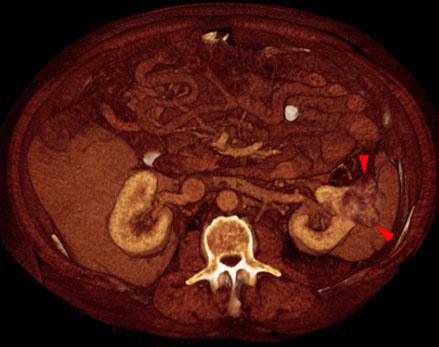

Pequeño hipernefroma